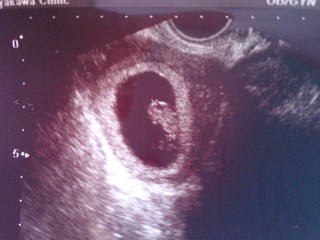

生理予定日から言うとちょうど9週なのですが、排卵も4日ほど遅れてたので検診に行ったらやはり8w4dくらいとの事。それでも2週間前は5.1mmだったのに今は16.8mmまで成長(*>ω<*)無事心拍も確認出来て念願の母子手帳GET♪

エコーは5dになってますが、大きさ的に4dみたいです。 前回の検診から3週あけての検診でした。

こんなに小さいのに心臓が元気に動いててかなり感動しました。 母子手帳もGETです

17.5mmです。切迫流産(絨毛膜下血腫)で入院中です。毎日不安ですが,診察のたびに元気な心拍と成長を見せてくれています。2回の稽留流産を経て,今度こそは元気に育ってほしい。赤ちゃんを信じて私も頑張ろうと思います。

この時のbabyの大きさが17.4mmぐらいです!

赤ちゃんの大きさ17㎜

8w0dでは11.7mmでやや遅れていて6週終わりから7週位と言われてましたが、8w4dでは丁度いい大きさで、心拍も160正常に動いてるとのことでした。